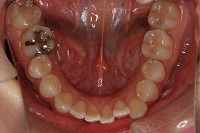

下顎

上の前歯が出ている事を主訴に来院された、23歳2か月の女性です。診断「下顎骨の後方回転による骨格性上顎前突で開咬を伴う」上顎は両側第1小臼歯、下顎は抜歯をせず治療を行いました。